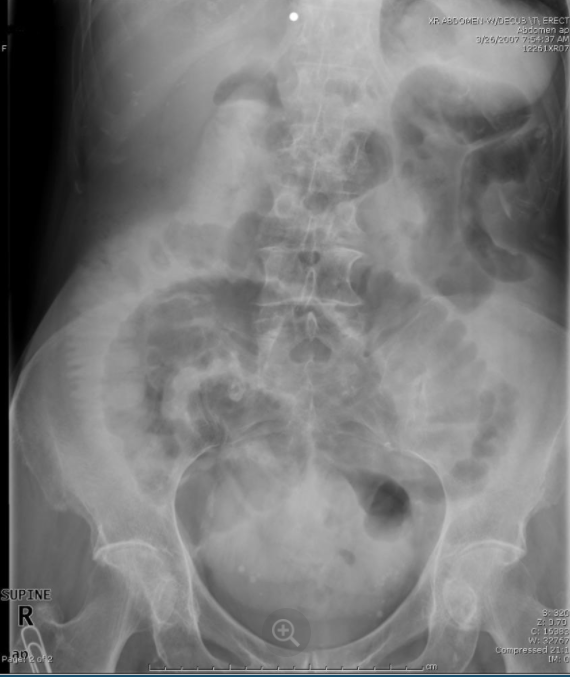

41

Obstrução de?

delgado

42

Colon